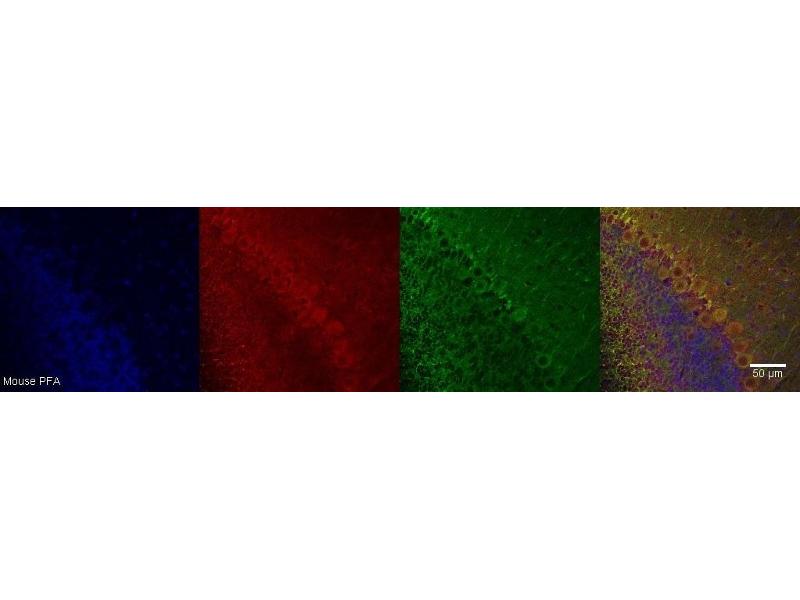

CRHR1 抗体

This 小鼠 单克隆 antibody specifically detects CRHR1 in IHC. It exhibits reactivity toward 人 和 小鼠.

Immunohistochemistry (IHC)